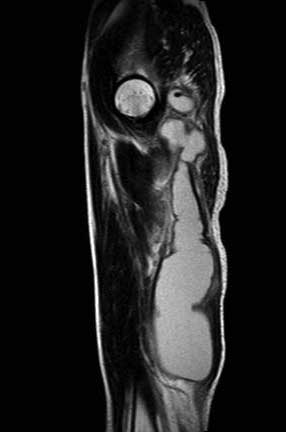

MRT - There is a ring enhancing multilobulated collection mainly within the left adductor

magnus muscle, this measures approximately 30 cm (CC) X 5cm (AP). The collection extends

superiorly into the pelvis and involves the left obturator internus muscle. There is

abnormal marrow signal within the posterior left acetabulum and inferior pubic ramus,

within the pubic ramus there appears to be an enhancing tract which may represent a cloaca. No

sinus tracts to the skin are seen. No definite abnormal signal is seen within the femur.